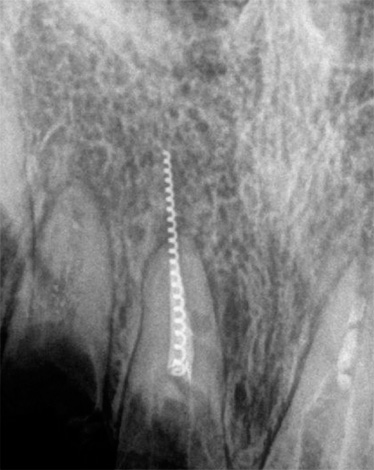

Foto de um dente de pulpite no início do tratamento e após a sua conclusão: